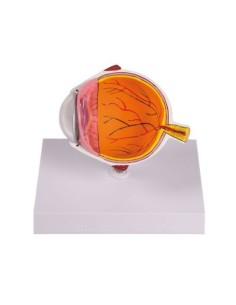

3B Scientific, modèle anatomique de l'œil, 5 fois agrandi, 6 pièces F10

3B Modèle anatomique scientifique de l'œil pathologique, agrandissement 5 fois F17

3B Modèle anatomique scientifique de l'œil dans l'orbite agrandi trois fois, en sept...

3B Scientific, modèle anatomique de l'œil en 6 parties, 5 fois agrandi VJ500C

3B Scientific, modèle anatomique de l'œil en 12 parties, 5 fois agrandi VJ500A

3B Modèle anatomique scientifique de l'œil agrandi 3 fois, en 6 parties F15

3B Modèle scientifique anatomique de l'œil, agrandi 5 fois, en 7 parties F11

3B Modèle scientifique anatomique de l'œil, agrandi 5 fois, en 8 parties F12